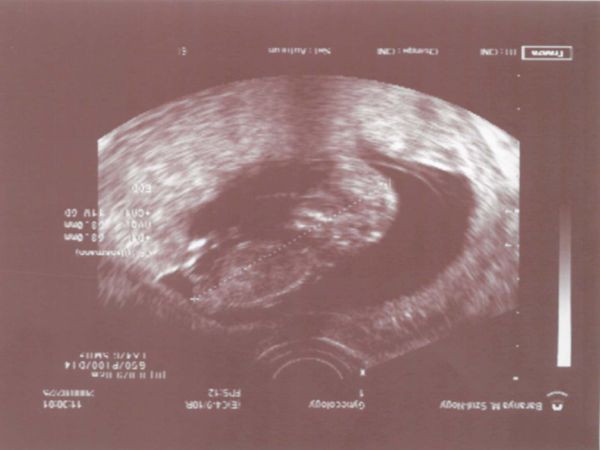

Vince baba igen, már 23 hetes a pocimban! Most már nagyon jól viselem a terhességet, hányinger teljesen megszűnt, álomkór szintúgy, ilyenkor aktívabb az ember, fészekrakás ösztöne hajt talán, vagy mi!